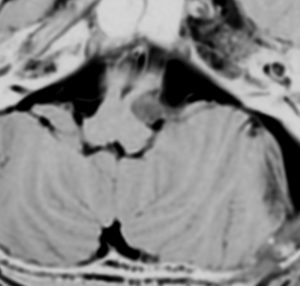

症例:延髄軟膜下 のもの subpial schwannoma in the medulla oblongata

40代男性です。咽せる,頚部痛という迷走神経症状で発症し,小脳失調がでてから腫瘍が発見されました。ある病院で第4脳室と脳槽内ののう胞性部分を摘出され,残存腫瘍摘出の目的で紹介されました。残った腫瘍は迷走神経根の腹側の延髄内部に食い込み,延髄軟膜下 subpial に主体がありました。nearly complete resectionをして経過を見ています。術後は嚥下障害が悪化したのですがかなり回復して,嗄声はなく自宅で食事をする日常生活にもどれました。